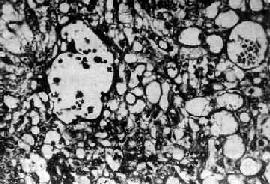

图13-23 内胚窦

呈疏松网状粘液样结构,其中有互相沟通、衬以上皮的腔隙及小囊腔,在细胞内外可见嗜酸性玻璃样小球及基底膜样物

肉眼观,肿多为单侧性,以右侧为多,一般体积较大,平均直径为15~25cm,圆或卵圆形,表面光滑。切面多为实性,质较脆,灰白或粉白色,常有出血坏死及囊性变。镜检,组织形态较复杂及特殊,主要特征有下列几点:①网状结构,是最常见的形态,由星芒状的细胞形成疏松网状结构(图13-23),其中有微型小囊或间隙,囊腔被覆扁平或立方细胞,这种结构类似胚外中胚层结构;②内胚窦样结构,立方或柱状的细胞成单层排列,包绕毛细血管,形成一血管套样结构,这种结构横切面很像肾小球,称为Schiller-Duval小体,这种小体和大鼠胎盘内的Duval内胚窦结构相似,这种结构可能是由卵黄囊衍生演变而来;③多泡性卵黄囊样结构,特征是由扁平上皮、立方或低柱状的细胞形成大小不等的囊腔,其间隔以致密的结缔组织或疏松的粘液样间质,这种结构与胚胎时期的卵黄囊(胚外内胚层)相似;④在细胞内及细胞间隙可见PAS阳性的大小不等的嗜酸性小滴,免疫组化显示这种小滴含有甲胎蛋白(AFP),正常情况下,卵黄囊可合成AFP;⑤可见腺样、乳头状及实体细胞团结构等。